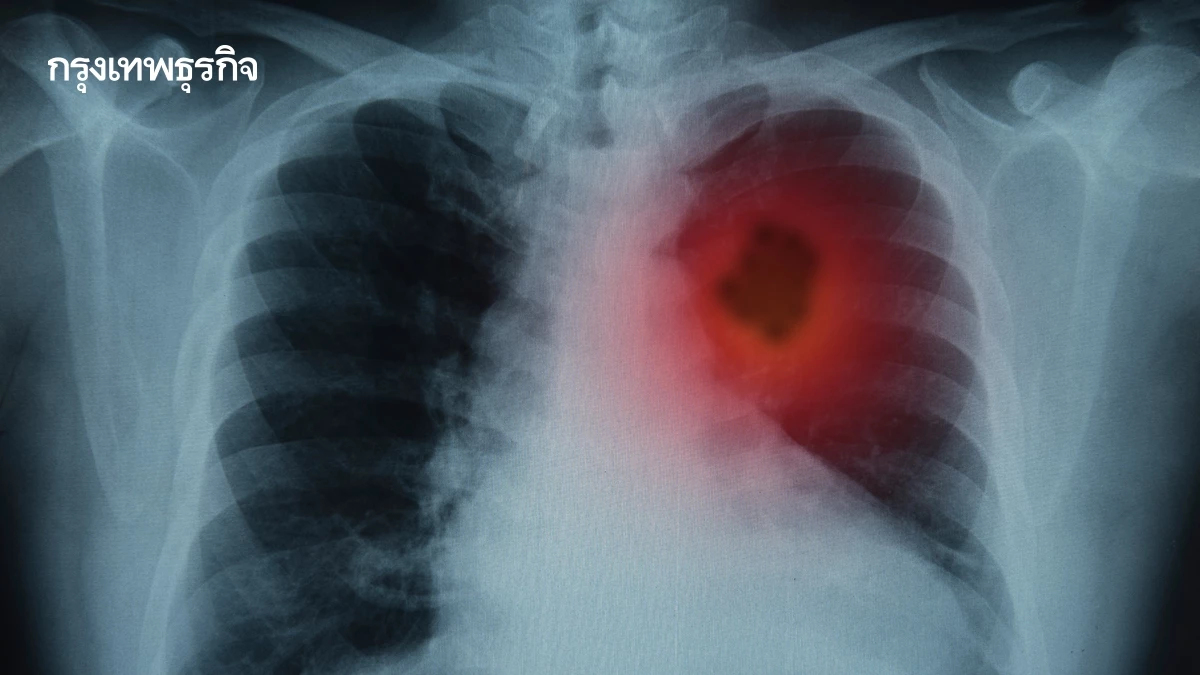

มะเร็งปอด PM2.5 ตัวปัญหา ไม่สูบบุหรี่ก็เป็นได้ เปิด 10 สัญญาณเตือน

ระวังภัยเงียบ "มะเร็งปอด" ไม่สูบบุหรี่ก็เป็นได้ เปิด 10 สัญญาณเตือน วิธีป้องกัน "หมอเจด" ชี้ PM2.5 ตัวปัญหาสำคัญ และ 5 สิ่งในบ้าน ต้นเหตุร้ายใกล้ตัว

ภัยเงียบ "มะเร็งปอด" หมอเจด เปิด 10 เรื่องที่ทุกคนต้องรู้

"หมอเจด" หรือ นพ.เจษฎ์ บุณยวงศ์วิโรจน์ รองผู้อำนวยการโรงพยาบาลมหาราช นครราชสีมา ได้ออกมาเปิดเผยข้อมูลสุขภาพที่สำคัญ เพื่อให้ประชาชนได้ตระหนักถึงภัยเงียบ "มะเร็งปอด" ผ่านเพจเฟซบุ๊ก "หมอเจด" โดยได้สรุป 10 เรื่องที่ควรรู้เกี่ยวกับมะเร็งปอด ดังนี้

5. ฝุ่น PM2.5 และควันจากการทำอาหารในบ้าน ก็เพิ่มความเสี่ยงได้ เอาจริงๆทุกวันนี้อยากจะบอกว่าถ้าไม่เห็นควันก็ไม่ได้แปลว่า PM 2.5 มันดีนะ บางครั้งถ้าต้องออกแดดออกข้างนอกบ้านอย่าลืมพกหน้ากากเถอะ

6. มะเร็งปอดเป็นสาเหตุการตายอันดับต้น ๆ ของคนไทย ซึ่งที่ผ่านมาเป็นมะเร็งอันดับ 2 ของคนไทยแต่เชื่อว่าก็น่าจะอยู่แบบนี้แหละเพราะฝุ่น PM 2.5 มันเป็นปัญหาที่สำคัญจริงๆ